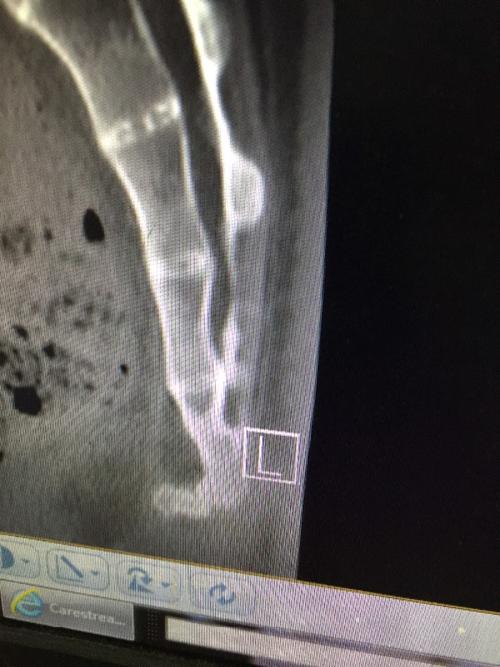

十七年前从高处跌下,尾骨严重错位,最下面一节前倾呈90度,第二节严重

尾椎骨ct图

尾椎骨ct图片

骶尾骨骨折ct图片

骶尾骨ct图片